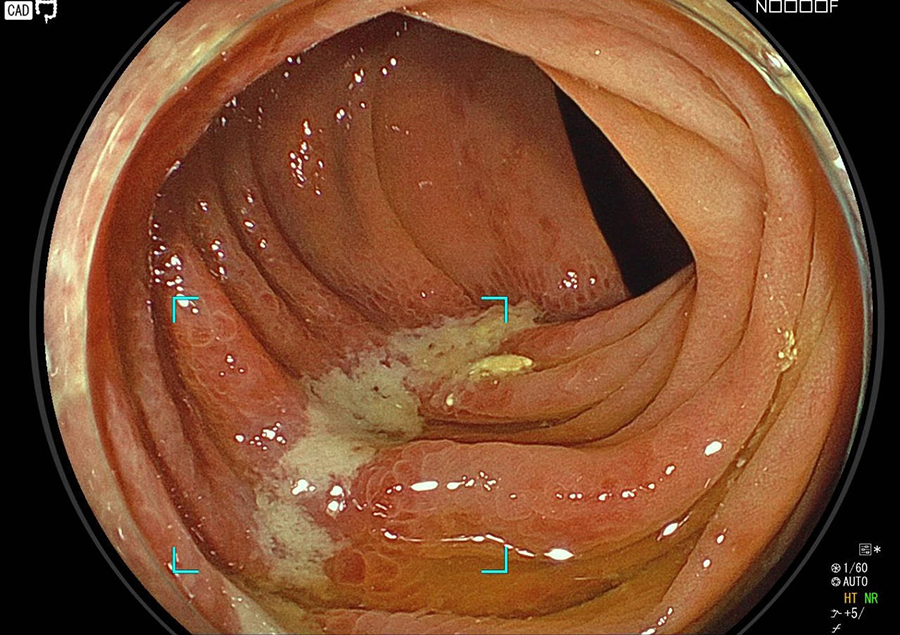

大腸カメラ検査では、肛門から内視鏡を挿入し、大腸、小腸の一部(回腸)を観察します。

大腸カメラはポリープやがんの発見と診断に、最も精度の高い検査法です。

大腸カメラ検査でわかる病気/病変